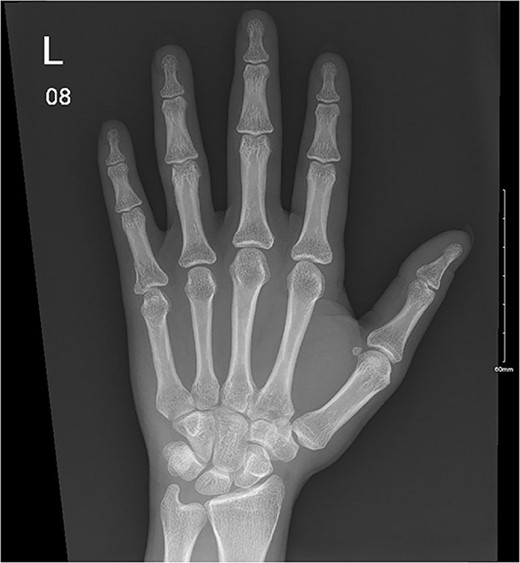

A 28-year-old female came to the emergency room (ER) following an MVA with airbag-deployment 5 days before presentation. Examination revealed tenderness at the base of the proximal fifth finger. The ROM of the affected digit was limited, but the neurovasculature as well as flexor digitorum profundus and flexor digitorum superficialis function were intact. X-ray of the hand showed a minimally displaced fracture at the base of the proximal fifth phalanx extending into the articular surface (Fig. 5). The decision was made to manage the patient conservatively by applying an ulnar gutter splint, which was then changed to a volar splint when the patient was followed-up in the clinic a week later. When the patient was last seen, the patient had limited ROM, and the tenderness had resolved. Imaging showed evidence of ongoing healing (Fig. 6).

A minimally displaced fracture at the base of proximal fifth phalanx extending into the articular surface.